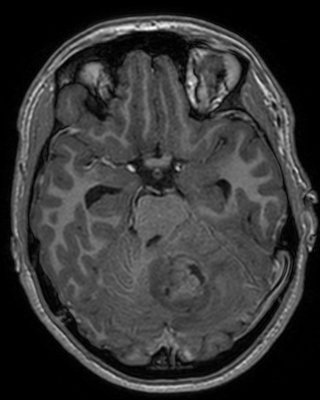

4.3 Evaluation on real low-dose images

Refer to captionRefer to caption𝐱PCsubscript𝐱PC\mathbf{x}_{\mathrm{PC}}bold_x start_POSTSUBSCRIPT roman_PC end_POSTSUBSCRIPTRefer to captionRefer to caption𝐱LDsubscript𝐱LD\mathbf{x}_{\mathrm{LD}}bold_x start_POSTSUBSCRIPT roman_LD end_POSTSUBSCRIPTRefer to captionRefer to caption𝐱SDsubscript𝐱SD\mathbf{x}_{\mathrm{SD}}bold_x start_POSTSUBSCRIPT roman_SD end_POSTSUBSCRIPTRefer to captionRefer to captionAm-3D [14]Refer to captionRefer to captionPa-2.5D [8]Refer to captionRefer to caption𝐱~SDsubscript~𝐱SD\tilde{\mathbf{x}}_{\mathrm{SD}}over~ start_ARG bold_x end_ARG start_POSTSUBSCRIPT roman_SD end_POSTSUBSCRIPT (ours)ptPhilips Achieva 3TGadobutrol dLD=0.10subscript𝑑LD0.10d_{\mathrm{LD}}=0.10italic_d start_POSTSUBSCRIPT roman_LD end_POSTSUBSCRIPT = 0.10ptPhilips Ingenia 1.5TGadoterate dLD=0.33subscript𝑑LD0.33d_{\mathrm{LD}}=0.33italic_d start_POSTSUBSCRIPT roman_LD end_POSTSUBSCRIPT = 0.33Refer to captionRefer to caption𝐱PCsubscript𝐱PC\mathbf{x}_{\mathrm{PC}}bold_x start_POSTSUBSCRIPT roman_PC end_POSTSUBSCRIPTRefer to captionRefer to caption𝐱LDsubscript𝐱LD\mathbf{x}_{\mathrm{LD}}bold_x start_POSTSUBSCRIPT roman_LD end_POSTSUBSCRIPTRefer to captionRefer to caption𝐱SDsubscript𝐱SD\mathbf{x}_{\mathrm{SD}}bold_x start_POSTSUBSCRIPT roman_SD end_POSTSUBSCRIPTRefer to captionRefer to captionAm-3D [14]Refer to captionRefer to captionPa-2.5D [8]Refer to captionRefer to caption𝐱~SDsubscript~𝐱SD\tilde{\mathbf{x}}_{\mathrm{SD}}over~ start_ARG bold_x end_ARG start_POSTSUBSCRIPT roman_SD end_POSTSUBSCRIPT (ours)ptPhilips Achieva 3TGadobutrol dLD=0.10subscript𝑑LD0.10d_{\mathrm{LD}}=0.10italic_d start_POSTSUBSCRIPT roman_LD end_POSTSUBSCRIPT = 0.10ptPhilips Ingenia 1.5TGadoterate dLD=0.33subscript𝑑LD0.33d_{\mathrm{LD}}=0.33italic_d start_POSTSUBSCRIPT roman_LD end_POSTSUBSCRIPT = 0.33Refer to captionRefer to caption𝐱PCsubscript𝐱PC\mathbf{x}_{\mathrm{PC}}bold_x start_POSTSUBSCRIPT roman_PC end_POSTSUBSCRIPTRefer to captionRefer to caption𝐱LDsubscript𝐱LD\mathbf{x}_{\mathrm{LD}}bold_x start_POSTSUBSCRIPT roman_LD end_POSTSUBSCRIPTRefer to captionRefer to caption𝐱SDsubscript𝐱SD\mathbf{x}_{\mathrm{SD}}bold_x start_POSTSUBSCRIPT roman_SD end_POSTSUBSCRIPTRefer to captionRefer to captionAm-3D [14]Refer to captionRefer to captionPa-2.5D [8]Refer to captionRefer to caption𝐱~SDsubscript~𝐱SD\tilde{\mathbf{x}}_{\mathrm{SD}}over~ start_ARG bold_x end_ARG start_POSTSUBSCRIPT roman_SD end_POSTSUBSCRIPT (ours)ptPhilips Achieva 3TGadobutrol dLD=0.10subscript𝑑LD0.10d_{\mathrm{LD}}=0.10italic_d start_POSTSUBSCRIPT roman_LD end_POSTSUBSCRIPT = 0.10ptPhilips Ingenia 1.5TGadoterate dLD=0.33subscript𝑑LD0.33d_{\mathrm{LD}}=0.33italic_d start_POSTSUBSCRIPT roman_LD end_POSTSUBSCRIPT = 0.33Refer to captionRefer to caption𝐱PCsubscript𝐱PC\mathbf{x}_{\mathrm{PC}}bold_x start_POSTSUBSCRIPT roman_PC end_POSTSUBSCRIPTRefer to captionRefer to caption𝐱LDsubscript𝐱LD\mathbf{x}_{\mathrm{LD}}bold_x start_POSTSUBSCRIPT roman_LD end_POSTSUBSCRIPTRefer to captionRefer to caption𝐱SDsubscript𝐱SD\mathbf{x}_{\mathrm{SD}}bold_x start_POSTSUBSCRIPT roman_SD end_POSTSUBSCRIPTRefer to captionRefer to captionAm-3D [14]Refer to captionRefer to captionPa-2.5D [8]Refer to captionRefer to caption𝐱~SDsubscript~𝐱SD\tilde{\mathbf{x}}_{\mathrm{SD}}over~ start_ARG bold_x end_ARG start_POSTSUBSCRIPT roman_SD end_POSTSUBSCRIPT (ours)ptPhilips Achieva 3TGadobutrol dLD=0.10subscript𝑑LD0.10d_{\mathrm{LD}}=0.10italic_d start_POSTSUBSCRIPT roman_LD end_POSTSUBSCRIPT = 0.10ptPhilips Ingenia 1.5TGadoterate dLD=0.33subscript𝑑LD0.33d_{\mathrm{LD}}=0.33italic_d start_POSTSUBSCRIPT roman_LD end_POSTSUBSCRIPT = 0.33Refer to captionRefer to caption𝐱PCsubscript𝐱PC\mathbf{x}_{\mathrm{PC}}bold_x start_POSTSUBSCRIPT roman_PC end_POSTSUBSCRIPTRefer to captionRefer to caption𝐱LDsubscript𝐱LD\mathbf{x}_{\mathrm{LD}}bold_x start_POSTSUBSCRIPT roman_LD end_POSTSUBSCRIPTRefer to captionRefer to caption𝐱SDsubscript𝐱SD\mathbf{x}_{\mathrm{SD}}bold_x start_POSTSUBSCRIPT roman_SD end_POSTSUBSCRIPTRefer to captionRefer to captionAm-3D [14]Refer to captionRefer to captionPa-2.5D [8]Refer to captionRefer to caption𝐱~SDsubscript~𝐱SD\tilde{\mathbf{x}}_{\mathrm{SD}}over~ start_ARG bold_x end_ARG start_POSTSUBSCRIPT roman_SD end_POSTSUBSCRIPT (ours)ptPhilips Achieva 3TGadobutrol dLD=0.10subscript𝑑LD0.10d_{\mathrm{LD}}=0.10italic_d start_POSTSUBSCRIPT roman_LD end_POSTSUBSCRIPT = 0.10ptPhilips Ingenia 1.5TGadoterate dLD=0.33subscript𝑑LD0.33d_{\mathrm{LD}}=0.33italic_d start_POSTSUBSCRIPT roman_LD end_POSTSUBSCRIPT = 0.33Refer to captionRefer to caption𝐱PCsubscript𝐱PC\mathbf{x}_{\mathrm{PC}}bold_x start_POSTSUBSCRIPT roman_PC end_POSTSUBSCRIPTRefer to captionRefer to caption𝐱LDsubscript𝐱LD\mathbf{x}_{\mathrm{LD}}bold_x start_POSTSUBSCRIPT roman_LD end_POSTSUBSCRIPTRefer to captionRefer to caption𝐱SDsubscript𝐱SD\mathbf{x}_{\mathrm{SD}}bold_x start_POSTSUBSCRIPT roman_SD end_POSTSUBSCRIPTRefer to captionRefer to captionAm-3D [14]Refer to captionRefer to captionPa-2.5D [8]Refer to captionRefer to caption𝐱~SDsubscript~𝐱SD\tilde{\mathbf{x}}_{\mathrm{SD}}over~ start_ARG bold_x end_ARG start_POSTSUBSCRIPT roman_SD end_POSTSUBSCRIPT (ours)ptPhilips Achieva 3TGadobutrol dLD=0.10subscript𝑑LD0.10d_{\mathrm{LD}}=0.10italic_d start_POSTSUBSCRIPT roman_LD end_POSTSUBSCRIPT = 0.10ptPhilips Ingenia 1.5TGadoterate dLD=0.33subscript𝑑LD0.33d_{\mathrm{LD}}=0.33italic_d start_POSTSUBSCRIPT roman_LD end_POSTSUBSCRIPT = 0.33Refer to captionRefer to caption𝐱PCsubscript𝐱PC\mathbf{x}_{\mathrm{PC}}bold_x start_POSTSUBSCRIPT roman_PC end_POSTSUBSCRIPTRefer to captionRefer to caption𝐱LDsubscript𝐱LD\mathbf{x}_{\mathrm{LD}}bold_x start_POSTSUBSCRIPT roman_LD end_POSTSUBSCRIPTRefer to captionRefer to caption𝐱SDsubscript𝐱SD\mathbf{x}_{\mathrm{SD}}bold_x start_POSTSUBSCRIPT roman_SD end_POSTSUBSCRIPTRefer to captionRefer to captionAm-3D [14]Refer to captionRefer to captionPa-2.5D [8]Refer to captionRefer to caption𝐱~SDsubscript~𝐱SD\tilde{\mathbf{x}}_{\mathrm{SD}}over~ start_ARG bold_x end_ARG start_POSTSUBSCRIPT roman_SD end_POSTSUBSCRIPT (ours)ptPhilips Achieva 3TGadobutrol dLD=0.10subscript𝑑LD0.10d_{\mathrm{LD}}=0.10italic_d start_POSTSUBSCRIPT roman_LD end_POSTSUBSCRIPT = 0.10ptPhilips Ingenia 1.5TGadoterate dLD=0.33subscript𝑑LD0.33d_{\mathrm{LD}}=0.33italic_d start_POSTSUBSCRIPT roman_LD end_POSTSUBSCRIPT = 0.33

Figure 6: Qualitative evaluation on the RLS dataset. The top row depicts a 33%percent3333\%33 % low-dose sample, where the yellow zoom highlights the lesion. The bottom row shows a case with a 10%percent1010\%10 % real low-dose image and the lesion is marked by the yellow circles.

Next, Am-3D, Pa-2.5D, and our approach trained on the RLD dataset are evaluated on the 77777777 RLD test images. Here, ADC images are additionally fed into Am-3D as required [14].

A qualitative comparison of RLD test samples is shown in Figure 6. The required skull stripping and non-linear intensity normalization of Am-3D are readily apparent. Thus, a quantitative comparison to the target 𝐱SDsubscript𝐱SD\mathbf{x}_{\mathrm{SD}}bold_x start_POSTSUBSCRIPT roman_SD end_POSTSUBSCRIPT is not reasonable. Nevertheless, the CE signal strength in pathological regions (highlighted by the yellow circles) is well visible despite too smooth output images. The internal morphology and the border delineation also exhibit blurring. Pa-2.5D yields better image quality but the contrast strength in pathological regions is not well captured. In particular, the contrast signal overshoots for the 33%percent3333\%33 % low-dose scan in the first row and undershoots for the 10%percent1010\%10 % scan at the bottom, although the training dataset contains low-dose images at both dose levels. Our approach yields the highest image quality and predicts the contrast enhancement more accurately due to the focus on the enhancement signal and the conditional embeddings. As a result, our approach generates CE images preserving the image quality of the inputs by avoiding the synthesis of anatomical or noise patterns.